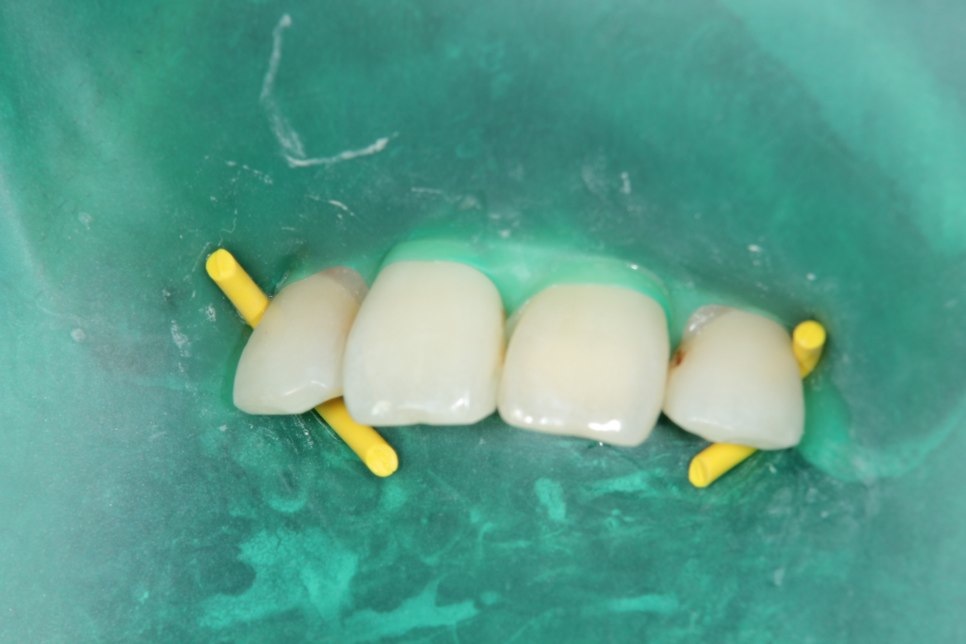

前歯の虫歯です。唾液の量が多い方や歯ぐきから出血がある方にはラバーダム防湿法を使います。このように緑色のゴムのシートを使用して、歯に唾液や血液が付かない様にします。

虫歯をとったところです。

無事治療が終わりました。削った穴に唾液や血液が入り込むと接着力が低下してしまいます。今回、削った穴に汚れが付く事無く、審美的な治療が出来ました。

ダイレクトボンディング

費用2万円×2本

リスクとして変色や欠ける可能性がある(修復可能)。